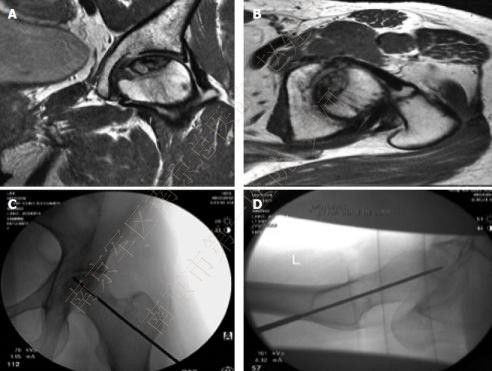

带血管蒂大粗隆移植骨(greater trochanter vascularized graft,GTVG):清除死骨后将带有旋股外侧动脉横支的大粗隆移植骨自头颈交界处开窗植入。Zhao对191例患者随访8年,最终只有23例患者再次行全髋置换,118例患者病情未见进展。

A DSA显示旋股外侧动脉穿支;B)DSA显示股骨头供血不足,但旋股外侧动脉穿支状态良好;C)术后DSA显示带有旋股外侧动脉穿支的大粗隆已植入股骨头内;D)DSA显示股骨头内血管再生。

游离腓骨移植(free vascularized fibular graft,FVFG):侧卧位,前外侧弧形入路,解剖分离出旋股外侧动脉升支及伴行静脉,C臂机监视下自股骨近端外侧向颈内制备骨隧道,移除死骨,显露同侧腓骨,将带有腓动静脉血管的腓骨游离,植入骨隧道中,吻合血管。Judet对60例患者进行了18年的随访,仅52%效果良好,但40岁以下患者的成功率可达80%,Ficat II期、III期的成功率也能达80%,提示病人的选择对治疗效果的影响;Urbaniak也持相同看法,其224例患者中,Ficat I和II期的成功率达到88%,而III期和IV期患者的成功率则降到78%。